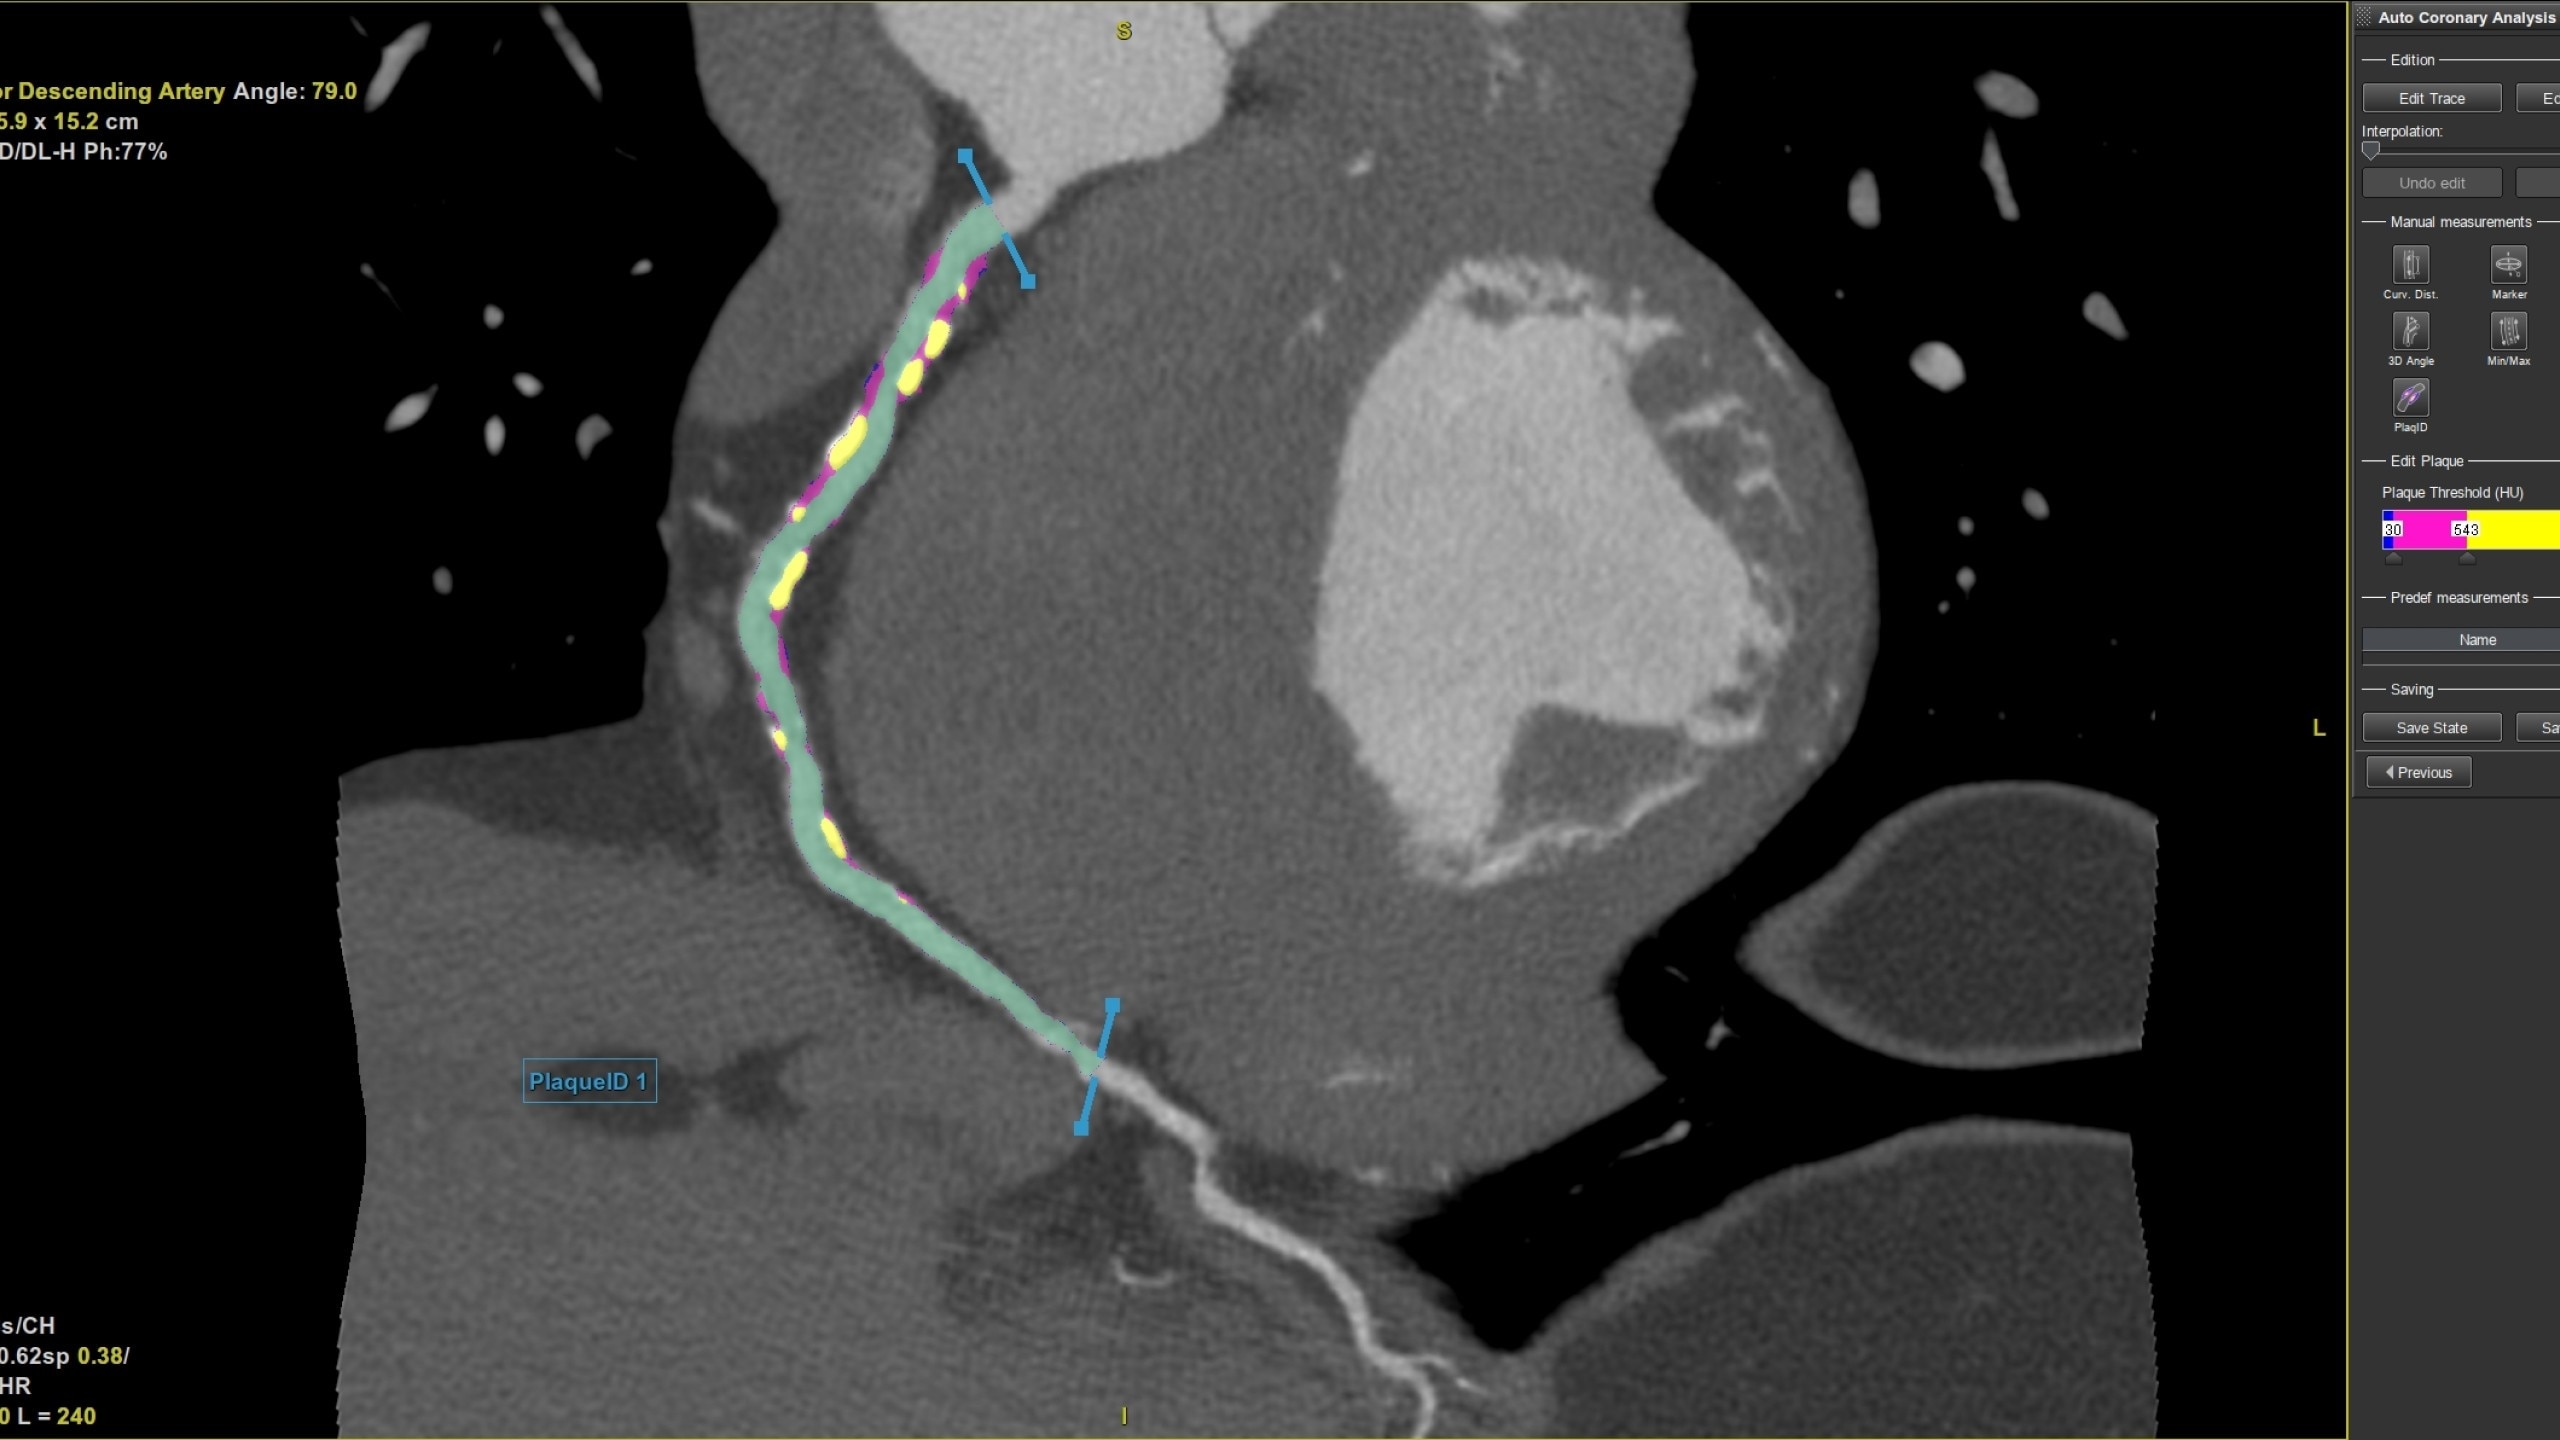

Coronary Plaque

Plaque ID tool assists in visualizing and quantifying plaque burden

• Plaque ID provides volume measurements for four

distinct Hounsfield ranges to aid with identification and

visualization of coronary plaque